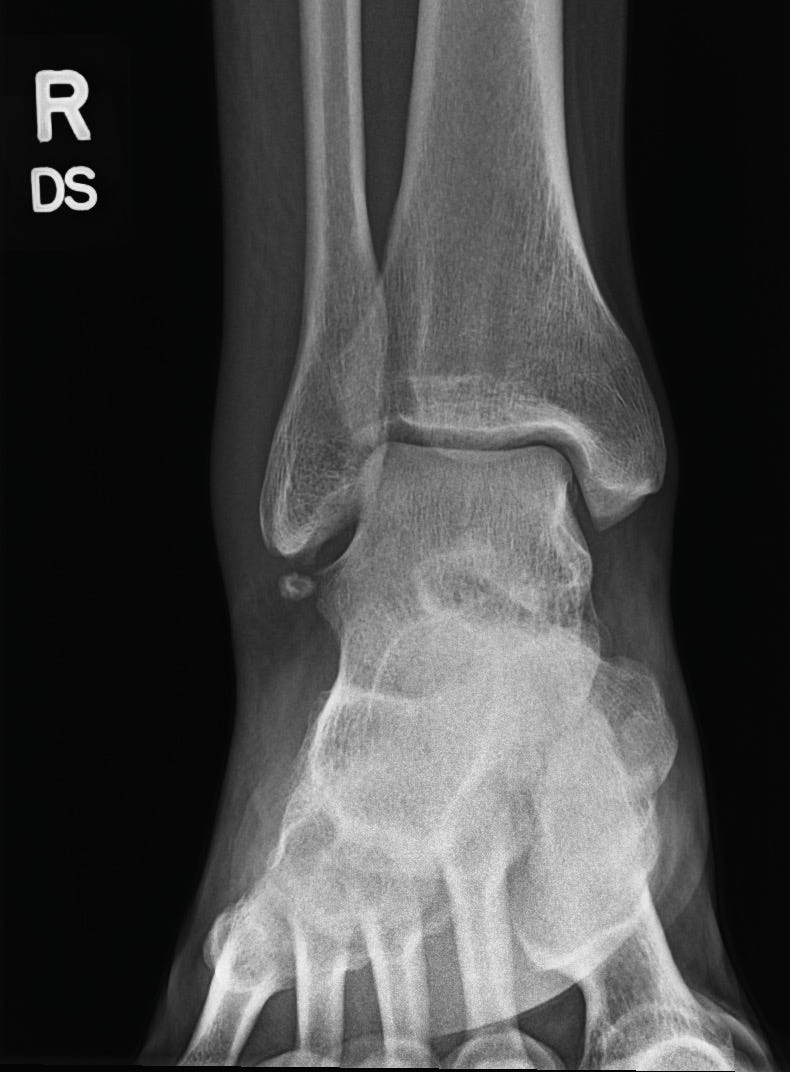

The swelling came fast. By the next day I couldnât bear weight, so off to the ER we went. X-rays. Waiting. Anxiety math.

Good news: no fracture.

Bad news: likely a grade-3 sprain.